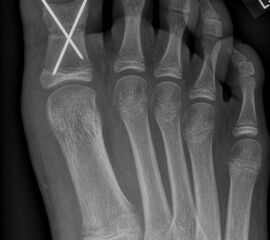

Zusätzlich schränken Wachstumsfugen die Wahl der Osteosynthese ein. Eine die Fuge kreuzende Osteosynthese ist ausschließlich mit Kirschner-Drähten möglich (Abb. 3).

Abb. 3 a-j: Beispiel einer Calcaneusverschiebeosteotomie mit offenen Wachstumsfugen und der entsprechenden Osteosynthese mit Kirschner Drähten. Lokalisation der Osteotomie (a), Lage der Fräse (b-d), Drahtlage mehrere Ansichten (e-h), Heilung der Osteotomie 4 Wochen postoperativ und Entfernung der Drähte (i-j).

Calcaneus-Osteotomie

Die minimalinvasive Calcaneusverschiebeosteotomie bietet eindeutige Vorteile gegenüber dem offenen Verfahren, sodass wir bei Kindern und Jugendlichen nahezu keine offene Verschiebeosteotomie mehr durchführen. Am Calcaneus liegt die offene Wachstumsfuge dorsal. Bei der Durchführung müssen Schenkel der V-förmigen Osteotomie daher etwas steiler angelegt werden, in einem stumpfen Winkel (siehe Abb. 3 a-j). Für die Osteotomie liegen unsere Patienten auf dem Rücken und der BV wird für die exakte Seitaufnahme eingestellt. Der Fuß lagert auf einem hohen OP-Kissen und die Osteotomie kann bequem mit einem langen Kirschner-Draht und einem sterilen Stift angezeichnet werden (Abb. 15).